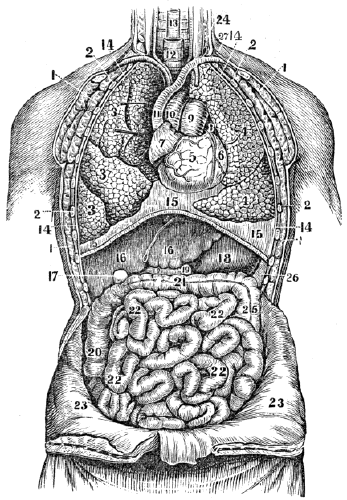

| 13. | Anatomy of the Digestive Organs, | 113 |

| 14. | Physiology of the Digestive Organs, | 124 |

| 15. | Hygiene of the Digestive Organs, | 129 |

| 16. | Hygiene of the Digestive Organs, continued, | 142 |

| 17. | Anatomy of the Circulatory Organs, | 154 |

| 18. | Physiology of the Circulatory Organs, | 164 |

| 19. | Hygiene of the Circulatory Organs, | 172 |

| 20. | Anatomy of the Lymphatic Vessels, | 181 |